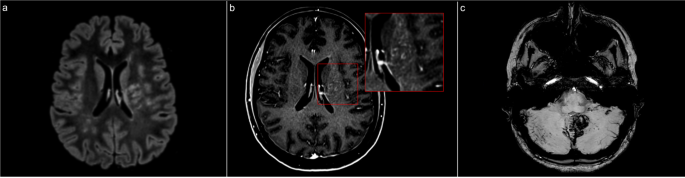

我们报告了一例24岁女性的病例,她因突发性持续性头痛(持续一个月)就诊于我们的三级医疗机构,同时伴有位置性眩晕和视力模糊。神经系统检查发现轻微的水平注视诱发眼球震颤,但没有局灶性缺陷。脑部MRI显示多个T2/FLAIR高信号灶,主要位于左侧壳核-脑豆状核区域和小脑蚓部。增强后序列显示点状、“胡椒状”的血管周围钆增强模式(图1,a面板和b面板)。此外,还观察到左侧小脑局灶性出血(图1,c面板)。

入院时进行的脑部MRI检查:a面板显示液体衰减反转恢复序列,显示主要位于左侧壳核-脑豆状核区域的高信号灶;b面板显示增强后T1加权序列,显示相同位置的点状血管周围钆增强(“胡椒状”);c面板显示磁化率加权成像序列,显示小脑蚓部上表面和左侧小脑蛛网膜下腔出血。